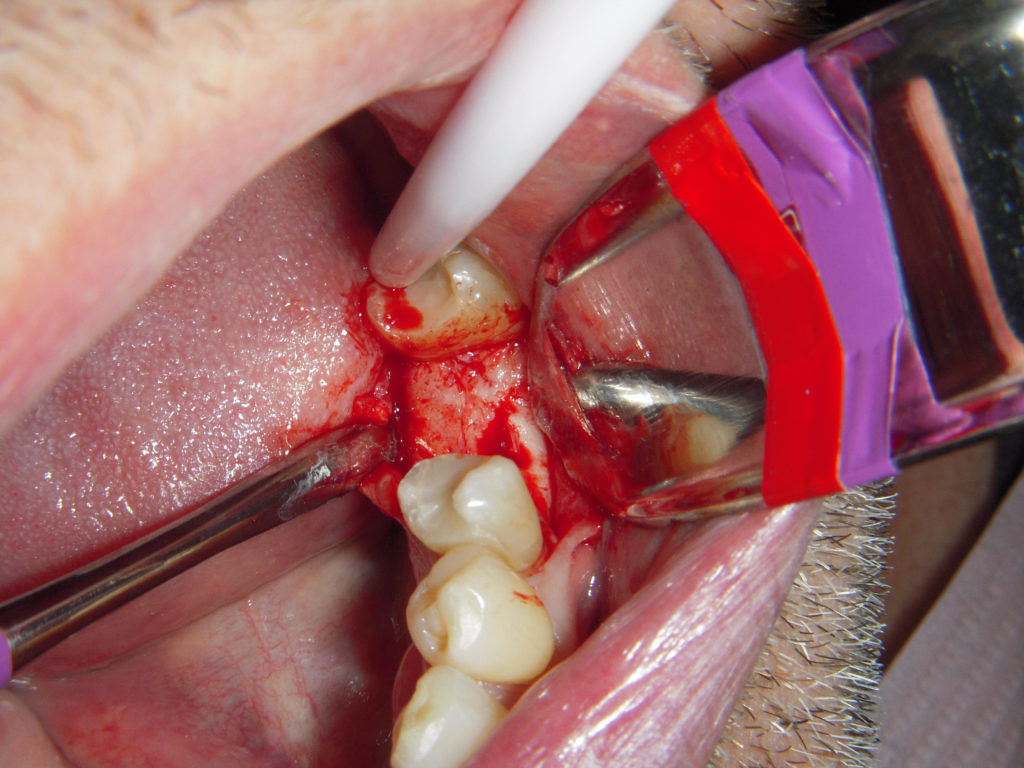

I took a photo of the decay and decalcification visible prior to finishing the prep.

Slot preps

As a side note, this photo is mid-decay removal. You will see from the upcoming radiogarphs, I do not do slot preps. Slot preps and restorations personally do not work well in my hands, and I find a lot of dentists have the same experience. When the decay is purely interproximal, I will still place a very small and shallow occlusion extension. There are plenty of different ways to get to the same excellent clinical result, but generally speaking I do not recommend slot preps (but aware there are dentists out there that have great results with them).